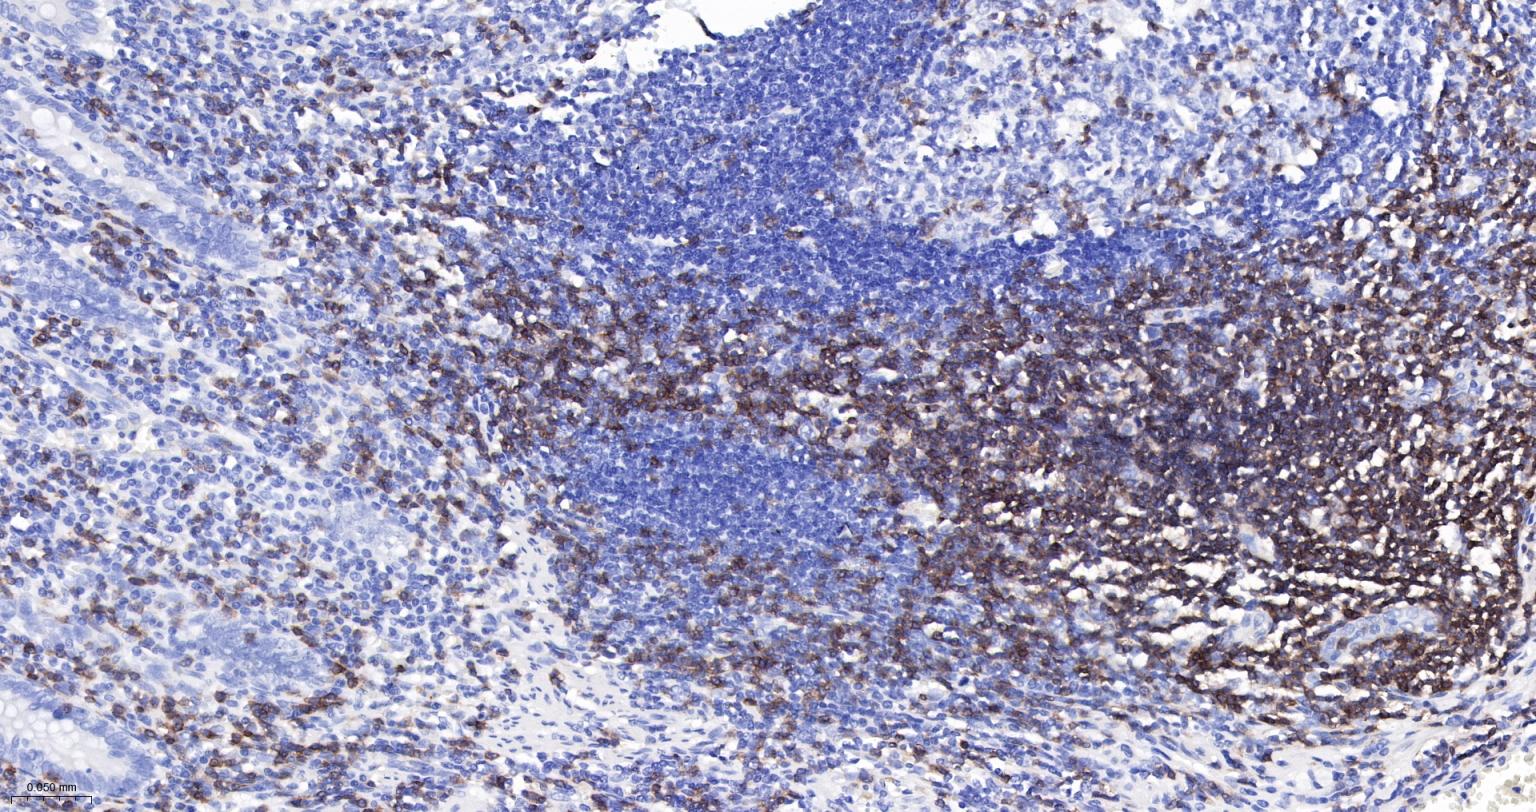

Paraformaldehyde-fixed, paraffin embedded Human Tonsil; Antigen retrieval by boiling in sodium citrate buffer (pH6.0) for 15 min; The section was incubated with CD3E Monoclonal Antibody, Unconjugated (bsm-54036M) at 1:200 overnight at 4°C, followed by conjugation to the bs-40296G-HRP and DAB (C-0010) staining.